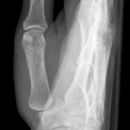

Finger d.-v. (D II-V) 1. Ebene

Indikation

Frakturen, Luxation, Osteosynthesematerial

Lagerung

sitzend - seitlich zum Tisch

abgewinkelte Unterarm und Hand liegen auf

Zentralstrahl

senkrecht auf Objektmitte

Einblendung

einschließlich Grundgelenk

Anmerkung

fragestellungsabhängige Einblendung

z. B. ganzer Strahl einschließlich Os metacarpale

Nummerierung des Fingers im Rö.-Bild z. B. D 2

Qualitätskriterien

Vollständige Abbildung des Fingers vom Grundgelenk bis zur Fingerkuppe mit überlagerungsfreiem Einblick in die Fingergelenke.